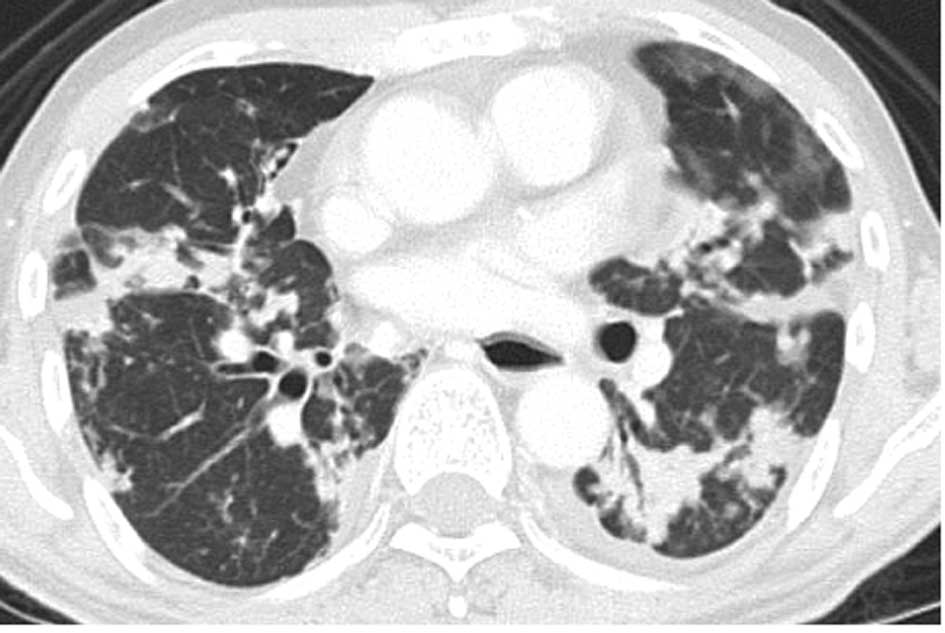

This article brings a broad view over lung adenocarcinoma for further details on each subtype please refer to the. Lin g xie c. Mucinous adenocarcinoma is the most enigmatic lung cancer with a wide radiological spectrum.

In one of the 12 patients pulmonary biopsy revealed mucinous adenocarcinoma but whether this was a primary lung cancer or a metastasis from an unknown primary carcinoma could not be determined. The hope is that she will go for a year or so without any recurrence or other problems. Invasive mucinous adenocarcinoma of the lung is a subtype of invasive adenocarcinoma of the lung formerly known as mucinous bronchoalveolar carcinoma bacthey are more likely to be multicentric and tend to have a worse prognosis than non mucinous types.

On radiograph and computed tomography ct polymorphic features of well differentiated adenocarcinomas formerly named bronchioloalveolar carcinomas are well known. When multifocal this cancer was formerly called multicentric bac. Adenocarcinoma of the lung is the most common histologic type of lung cancergrouped under the non small cell carcinomas of the lung it is a malignant tumor with glandular differentiation or mucin production expressing in different patterns and degrees of differentiation.